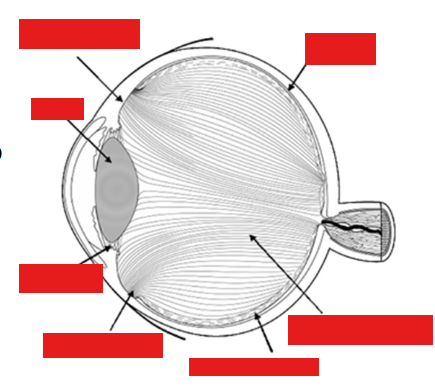

Label the eye

Retinal detachment and holes

Vitreo-retinal anatomy

98 % Water

Strongly adherent to retina at vitreous base, optic disc and along major vessels arcades

Danger if there’s a pull → bleeding into vitreous space/pre retinal space causing severe haemorrhaging

Type II collagen t½ 40yr

Type IX collagen t½ 11yr

→ clumping/reduction in vitreous size